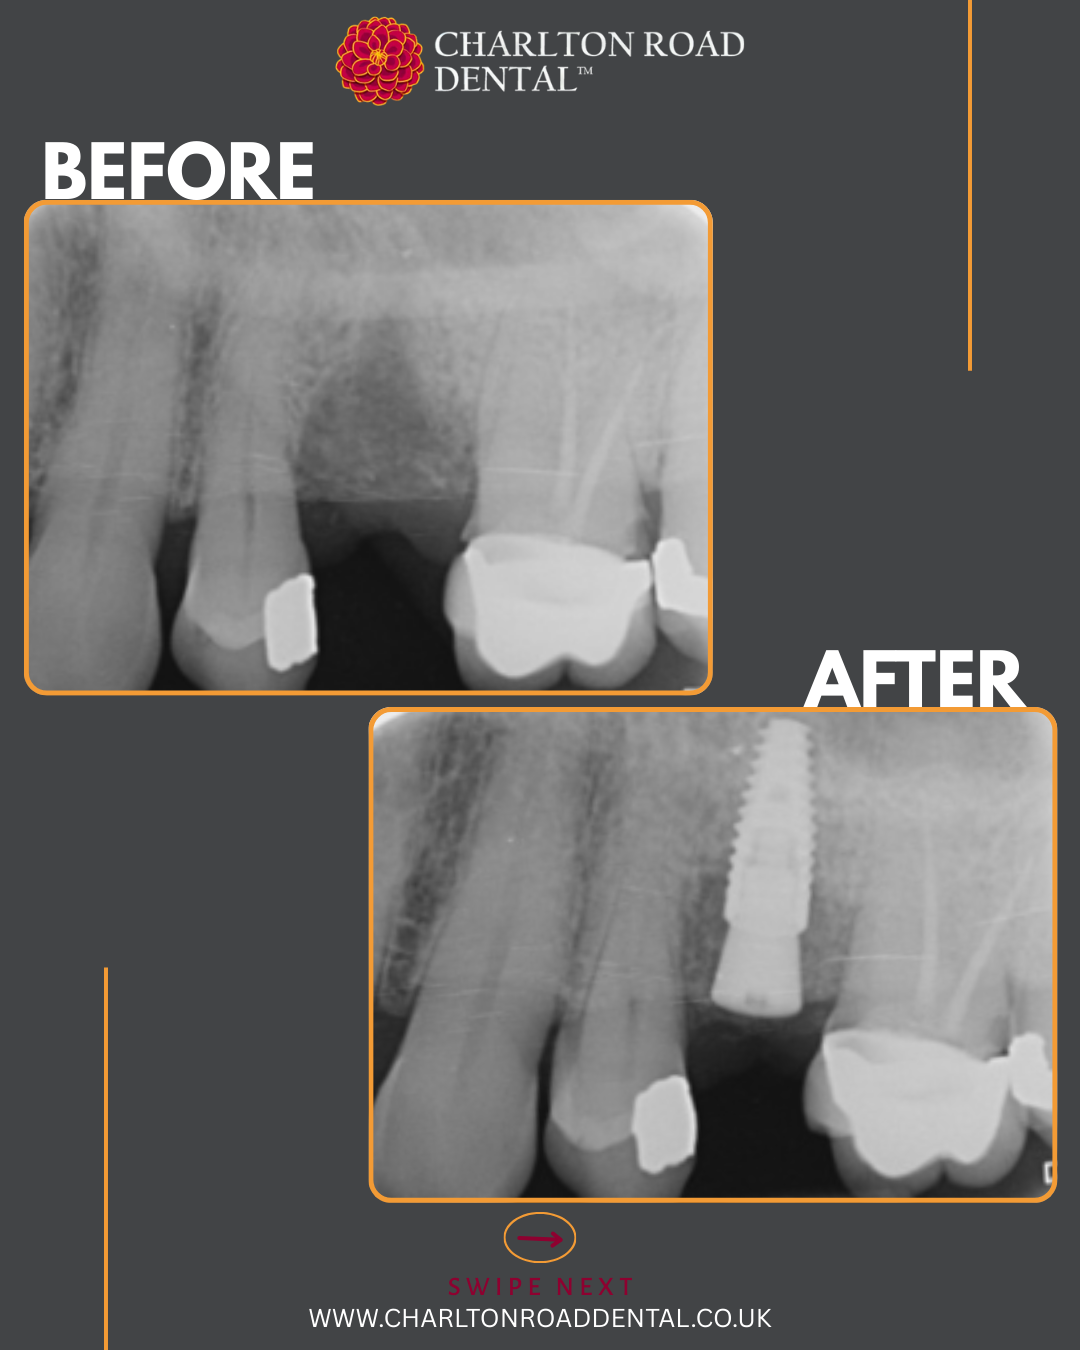

A week of implants @ Charlton Road Dental